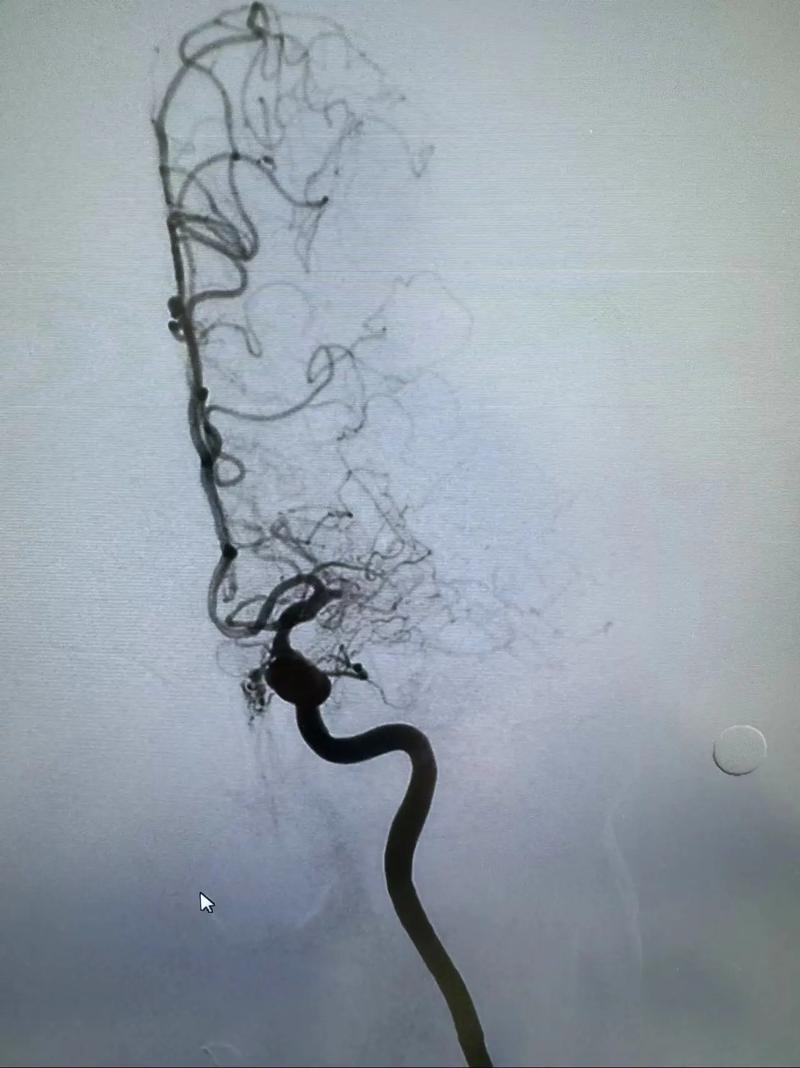

- DSA (数字减影血管造影):这是诊断脑血管病的“金标准”,在评估阶段,如果高度怀疑需要手术,医生可能会建议直接做DSA,一旦明确,即可同期进行支架植入术,避免患者再次住院。

- 入路:医生会从大腿根部的股动脉穿刺,插入一根细导管,沿着血管到达颈动脉或椎动脉的狭窄部位。

- 植入支架:在X光造影的引导下,将球囊扩张支架送到狭窄处,然后释放球囊撑开支架,使血管恢复通畅。